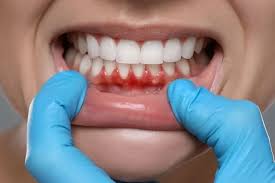

Diş eti çekilmesi (gingival retraksiyon), dişeti dokusunun diş kökü üzerinden geri çekilmesi ile karakterizedir. Hem mekanik hem de biyolojik faktörler bu sürece katkıda bulunur. Aşağıda detaylı şekilde açıklıyorum:

Diş Eti Çekilmesi: Nedenleri, Mekanizmaları ve Önleme Yöntemler Diş eti çekilmesi (gingival retraksiyon), dişeti dokusunun diş kökünden geri çekilmesiyle karakterizedir. Bu durum yalnızca estetik sorun yaratmakla kalmaz, aynı zamanda diş kökünün açığa çıkması nedeniyle hipersensitivite, çürük riski ve periodontal hastalık progresyonu gibi komplikasyonlara yol açabilir. Çekilmenin oluşumunda hem mekanik hem de biyolojik faktörler rol oynar.

- Diş plakları ve tartar (diş taşı) birikimi, gingivitis ve periodontitise yol açar.

- Gingivitis: Sadece dişetinde inflamasyon vardır, başlangıç aşamasında genellikle çekilme görülmez.

- Periodontitis: Dişeti ve alveolar kemiğin kaybına yol açan ileri inflamasyon, diş eti çekilmesinin en yaygın biyolojik nedenidir.

- Periodontal cep oluşumu ve kemik kaybı, dişetinin diş kökü üzerinden geri çekilmesini kolaylaştırır.